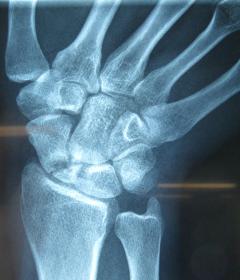

Η ψευδάρθρωση καταγμάτων του σκαφοειδούς δεν είναι σπάνια επιπλοκή (βλ αντίστοιχο κεφάλαιο). Λόγω ανατομικών και φυσιολογικών ιδιαιτεροτήτων του σκαφοειδούς ή λόγω υποτίμησης των ενοχλημάτων εκ μέρους του αρρώστου, το κάταγμα συχνά διαφεύγει της αρχικής διαγνώσεως. Αυτό οδηγεί σε ανεπαρκή αντιμετώπιση, η οποία καταλήγει σε μη πώρωση (ψευδάρθρωση) του σκαφοειδούς. Η κατάσταση αυτή αρχικά έχει ελαφρά ή καθόλου συμπτώματα, με την πάροδο όμως των ετών εγκαθίσταται προοδευτικά επώδυνος περιορισμός της κινητικότητας του καρπού και ελάττωση της δύναμης δραγμού (αδύναμο σφίξιμο σε γροθιά).

Οσο κοντύτερα προς τον αγκώνα είναι το κάταγμα (κατάγματα του κεντρικού πόλου) τόσο μεγαλύτερη είναι η πιθανότητα να εμφανισθεί και νέκρωση του κεντρικού πόλου λόγω διακοπής της αιμάτωσης (άσηπτη νέκρωση). Αυτό καθιστά ακόμη πιο δύσκολη τον χειρισμό της ψευδάρθρωσης.

Περίπτωση 2: Προεγχειρητικά